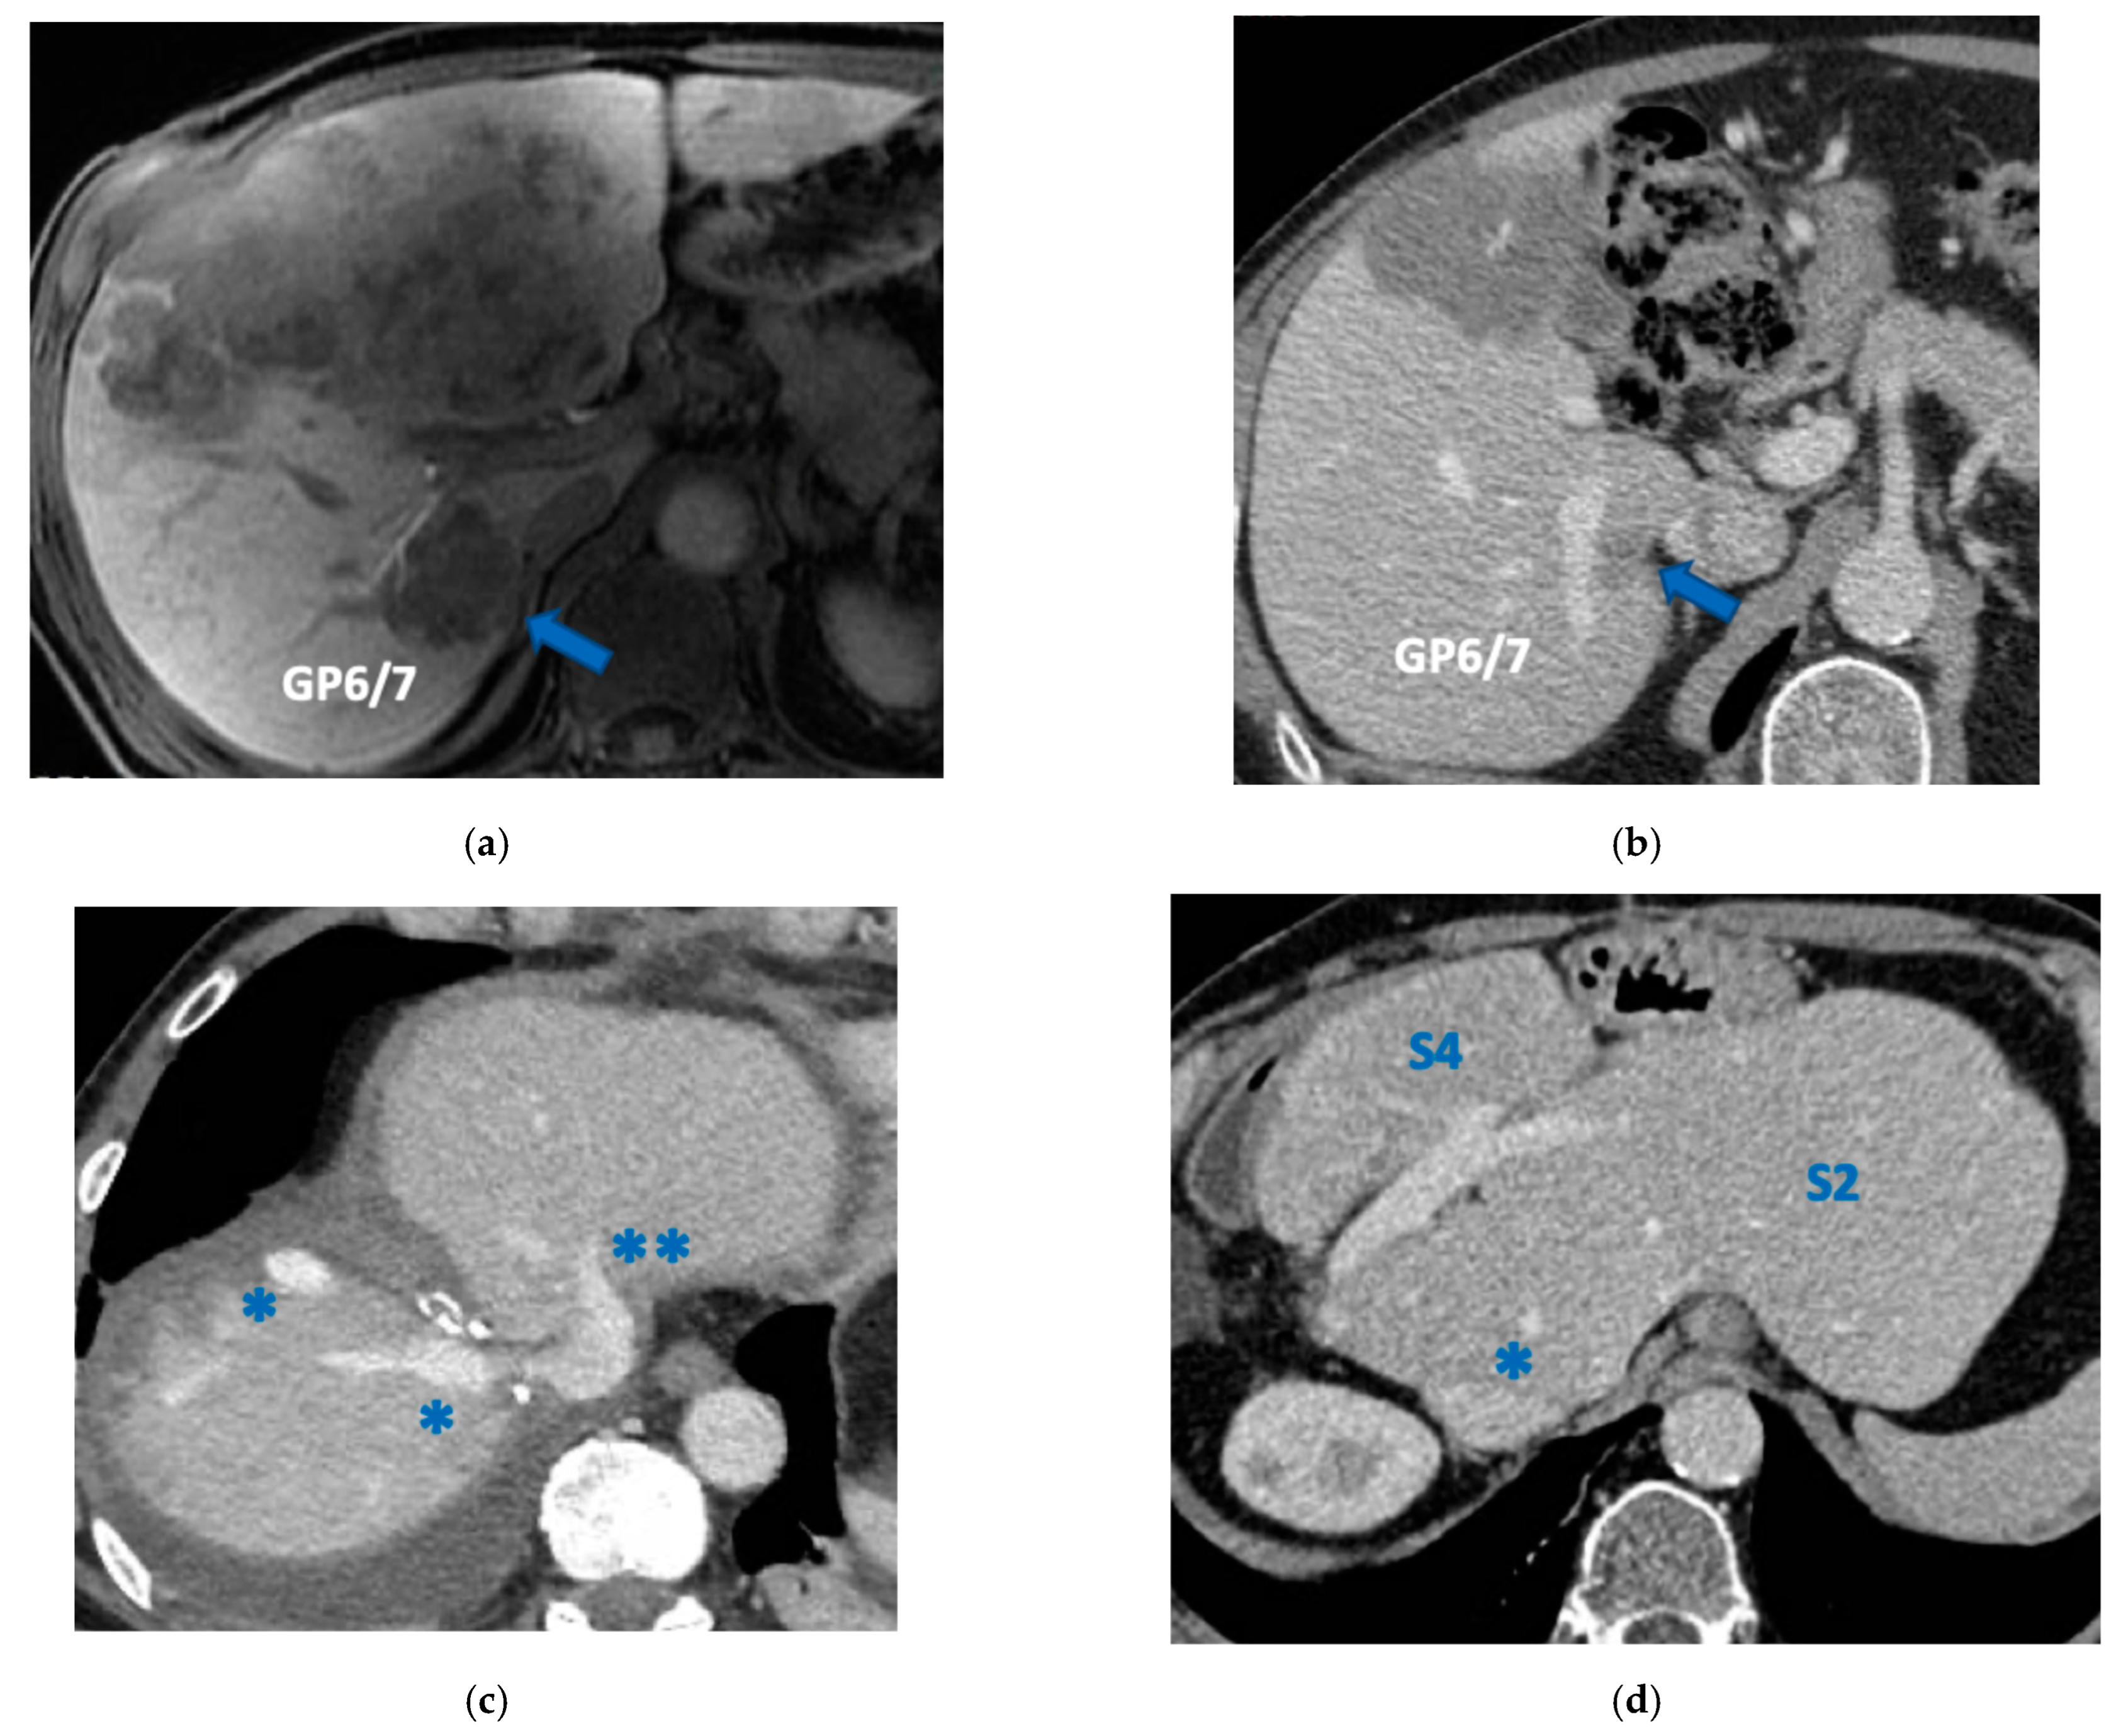

3.3. PS-TSH with SS-PVE

Super-selective portal vein embolization was performed in three patients since the resection of first-order GPs was deemed not necessary and a TWO-STAGE major PSH with SS-PVE was planned. Percutaneous PVE was achieved under US guidance via an ipsilateral approach through the tumor-bearing liver in two patients and via a contralateral approach through the future remnant liver in one patient. The accesses were respectively by S6, S5 and S3 portal vein branches under US guidance and local anesthesia. In all three cases S1/S4 were anatomically resected en-bloc with MHV at the first stage (MLP). Super-selective PVE consisted in embolization of portal branch for S6/S7/S8 in one case, for S7/S8 in one case and for S5/S8 in one case. The second stage was performed 58, 57 and 63 days after the first stage and consisted in the resection of S6/S7/S8 with RHV skeletonization in one case (see Figure 6 and Figure 7), in resection of S7/S8 partially extended to S5/S6 en-bloc with RHV reconstructed with an end-to-end anastomosis in one case (see Figure 8) and in resection of S7/S8/S5 en-bloc with RHV reconstructed with end-to-end anastomosis in another case. No complications occurred after surgery and patients were discharged from the hospital on the 11th, 11th and 17th post-operative day. The primary was resected at the time of the first stage (right hemicolectomy) in two cases and before the first stage (left hemicolectomy, “primary first” strategy) in one case.

In two cases of TWO-STAGE vessel-guided major PSH with super-selective PVE at the second stage RHV was reconstructed with an end-to-end anastomosis since RHV was resected with S7/S8 partially extended to S5/S6 in one case and with S7/S8/S5 in another case (Figure 8).

Our new PS-TSH is defined as parenchyma sparing because it aims at preserving a single segment in the right liver instead of performing extended right hepatectomy (Figure 1). Super-selective PVE was performed for the first time in this setting in three patients with favorable short-term outcome. PS-TSH was really well tolerated, in particular considering the highest complexity of the second stage (i.e., in a 77-year-old patient we have preserved S6 with end-to-end RHV reconstruction, Figure 8) as it is performed in one of the two livers while the other remains untouched. For the same reason, eventually repeated liver resections are technically demanding due to adhesions, but still feasible (i.e., a patient was re-resected once in the left liver and twice in the right).